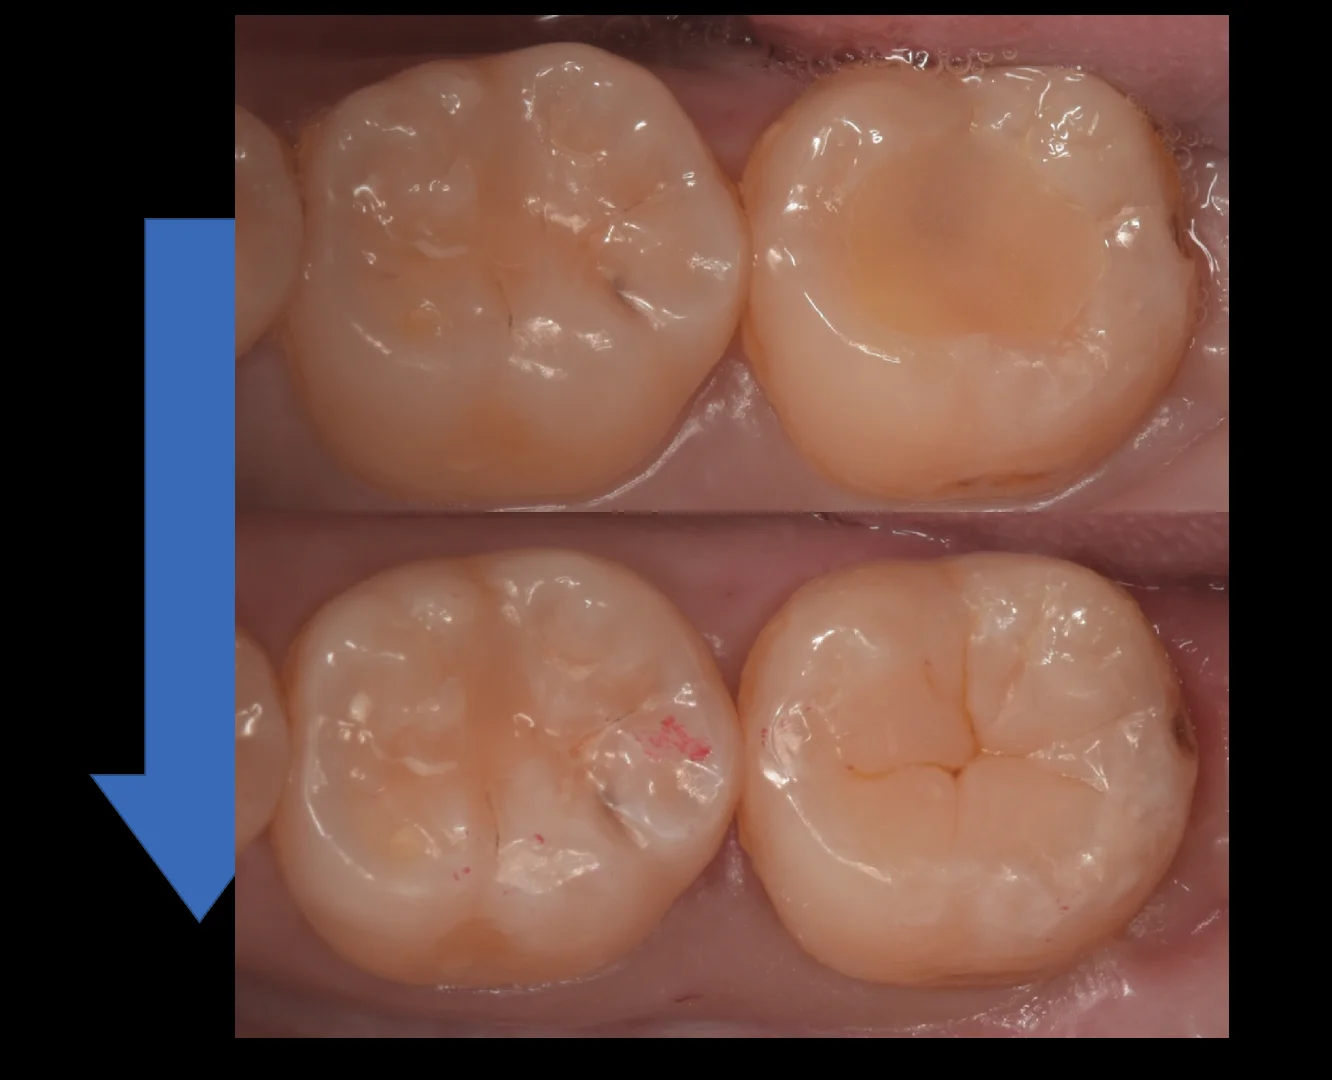

そして、詰め終わったのがこちらになります。

他の歯の溝の色をなるべく再現して同系統の色になるようにしました。

詰めたところの色が浮いているように見えますが、これは乾燥によるもので、1週間くらいで水分が戻ることで色が合ってきます。

術前術後の比較です。

いかがでしょうか?

比較的自然な形が入れられたのではないでしょうか?

患者さんにも喜んでいただけました。